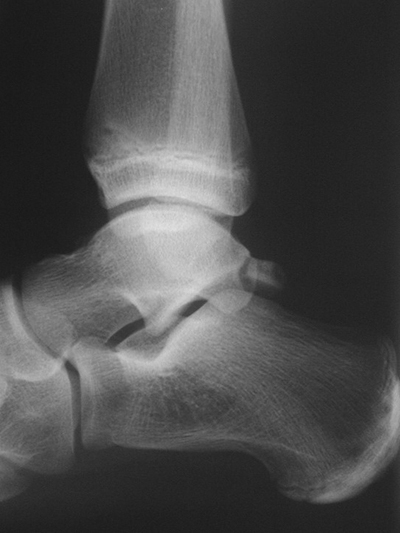

Röntgen

Die Standard Röntgendiagnostik des Sprunggelenks umfasst Bilder in anteriorposterioren (a.p.) und im seitlichen Strahlengang 6. Für die exakte Abbildung des Innenknöchels müssen beide Malleolen parallel zur Röntgenplatte zu liegen kommen. Je nach Torsion der Tibia macht dies eine Innenrotation des Fußes zwischen 10° und 30° erforderlich (Abb. 3).

Manchmal sind mediale Malleolarfrakturen nur in einer der Aufnahmen in ihrem Ausmaß erkennbar. Keine Rolle spielt die gehaltene Aufnahme beim Kind, insbesondere bei der akuten Verletzung. In seltenen Fällen hat dieses Verfahren bei Verdacht auf eine chronische Instabilität eine Berechtigung.

Fugengelenkfrakturen treten typischerweise vor dem 10. Lebensjahr auf, in einer Phase, in welcher die Wachstumsfugen noch weit offen sind. Dieser Frakturtyp betrifft fast ausschließlich den medialen Malleolus. Laterale Frakturen sind extrem selten, teilweise kommt es zu lateralen Bandverletzungen oder Fugenschaftfrakturen der distalen Fibula. Die Frakturlinie verläuft in einer Verlängerungslinie von der medialen Taluskante nach proximal. Häufig stellen sich Verletzungen des Innenknöchels im Röntgenbild schlechter dar, insbesondere wenn die Aufnahmen verdreht sind oder die Ebene der Fraktur bei geringer Dislokation verkippt zur Röntgenebene liegt. Besteht klinisch der geringste Hinweis auf eine Verletzung des Innenknöchels, muss aufgrund der Tragweite der Verletzung durch entsprechende Aufnahmen gegebenenfalls auch Schnittbildverfahren die Verletzung sicher diagnostiziert oder ausgeschlossen werden (Abb. 15).